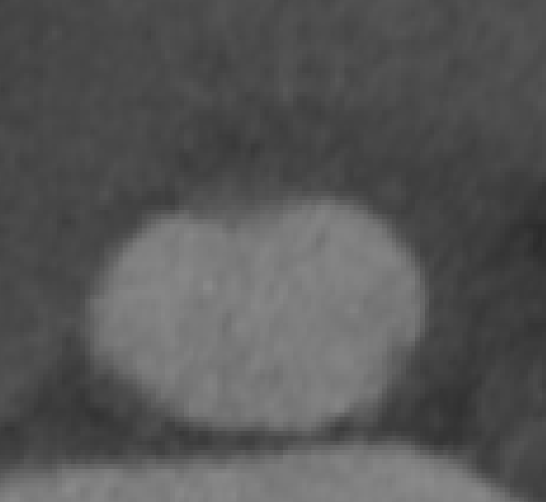

CT评估

瓣环直径:24.5mm,左室流出道直径:26.9mm